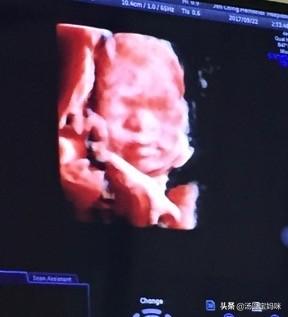

近日 , 安徽合肥一位准妈妈满怀期待的去医院做四维彩超 ,次因宝宝不配合翻身 , 医生叮嘱出来爬楼梯 , 爬了楼梯还是感觉不到动 , 就去买了支雪糕吃 。

然后继续爬楼梯 。 2个小时后 , 终于进去了 。 宝宝果然更配合了 。 但孕妈在看到宝宝的四维照后却哭的稀里哗啦 。 还边哭边说:“太丑了 , 没见过那么丑的小孩 。 ”

准爸爸原本也觉得丑 , 心里有点儿难受 。 但看到孕妈的反应却令他哭笑不得 。

于是赶忙安慰道:“孩子20多周长成这样已经很不容易了 , 有鼻有眼的 。 ”

特别能理解这位孕妈 。 毕竟当初我拍四维时 , 也是次没通过;吃了午饭后再重新排队做的检查 , 但看到宝宝照片的反应也是丑到不敢认 。 又大又扁的鼻梁 , 又宽又厚的嘴唇 , 总觉得是医生弄错了 。

【宝宝|准妈妈被自己宝宝彩超丑哭 还边哭边说没见过这么丑的】说实话 , 这也是大部分准妈妈的反应 。 因为拍4维的宝宝鲜有长得好看的 。